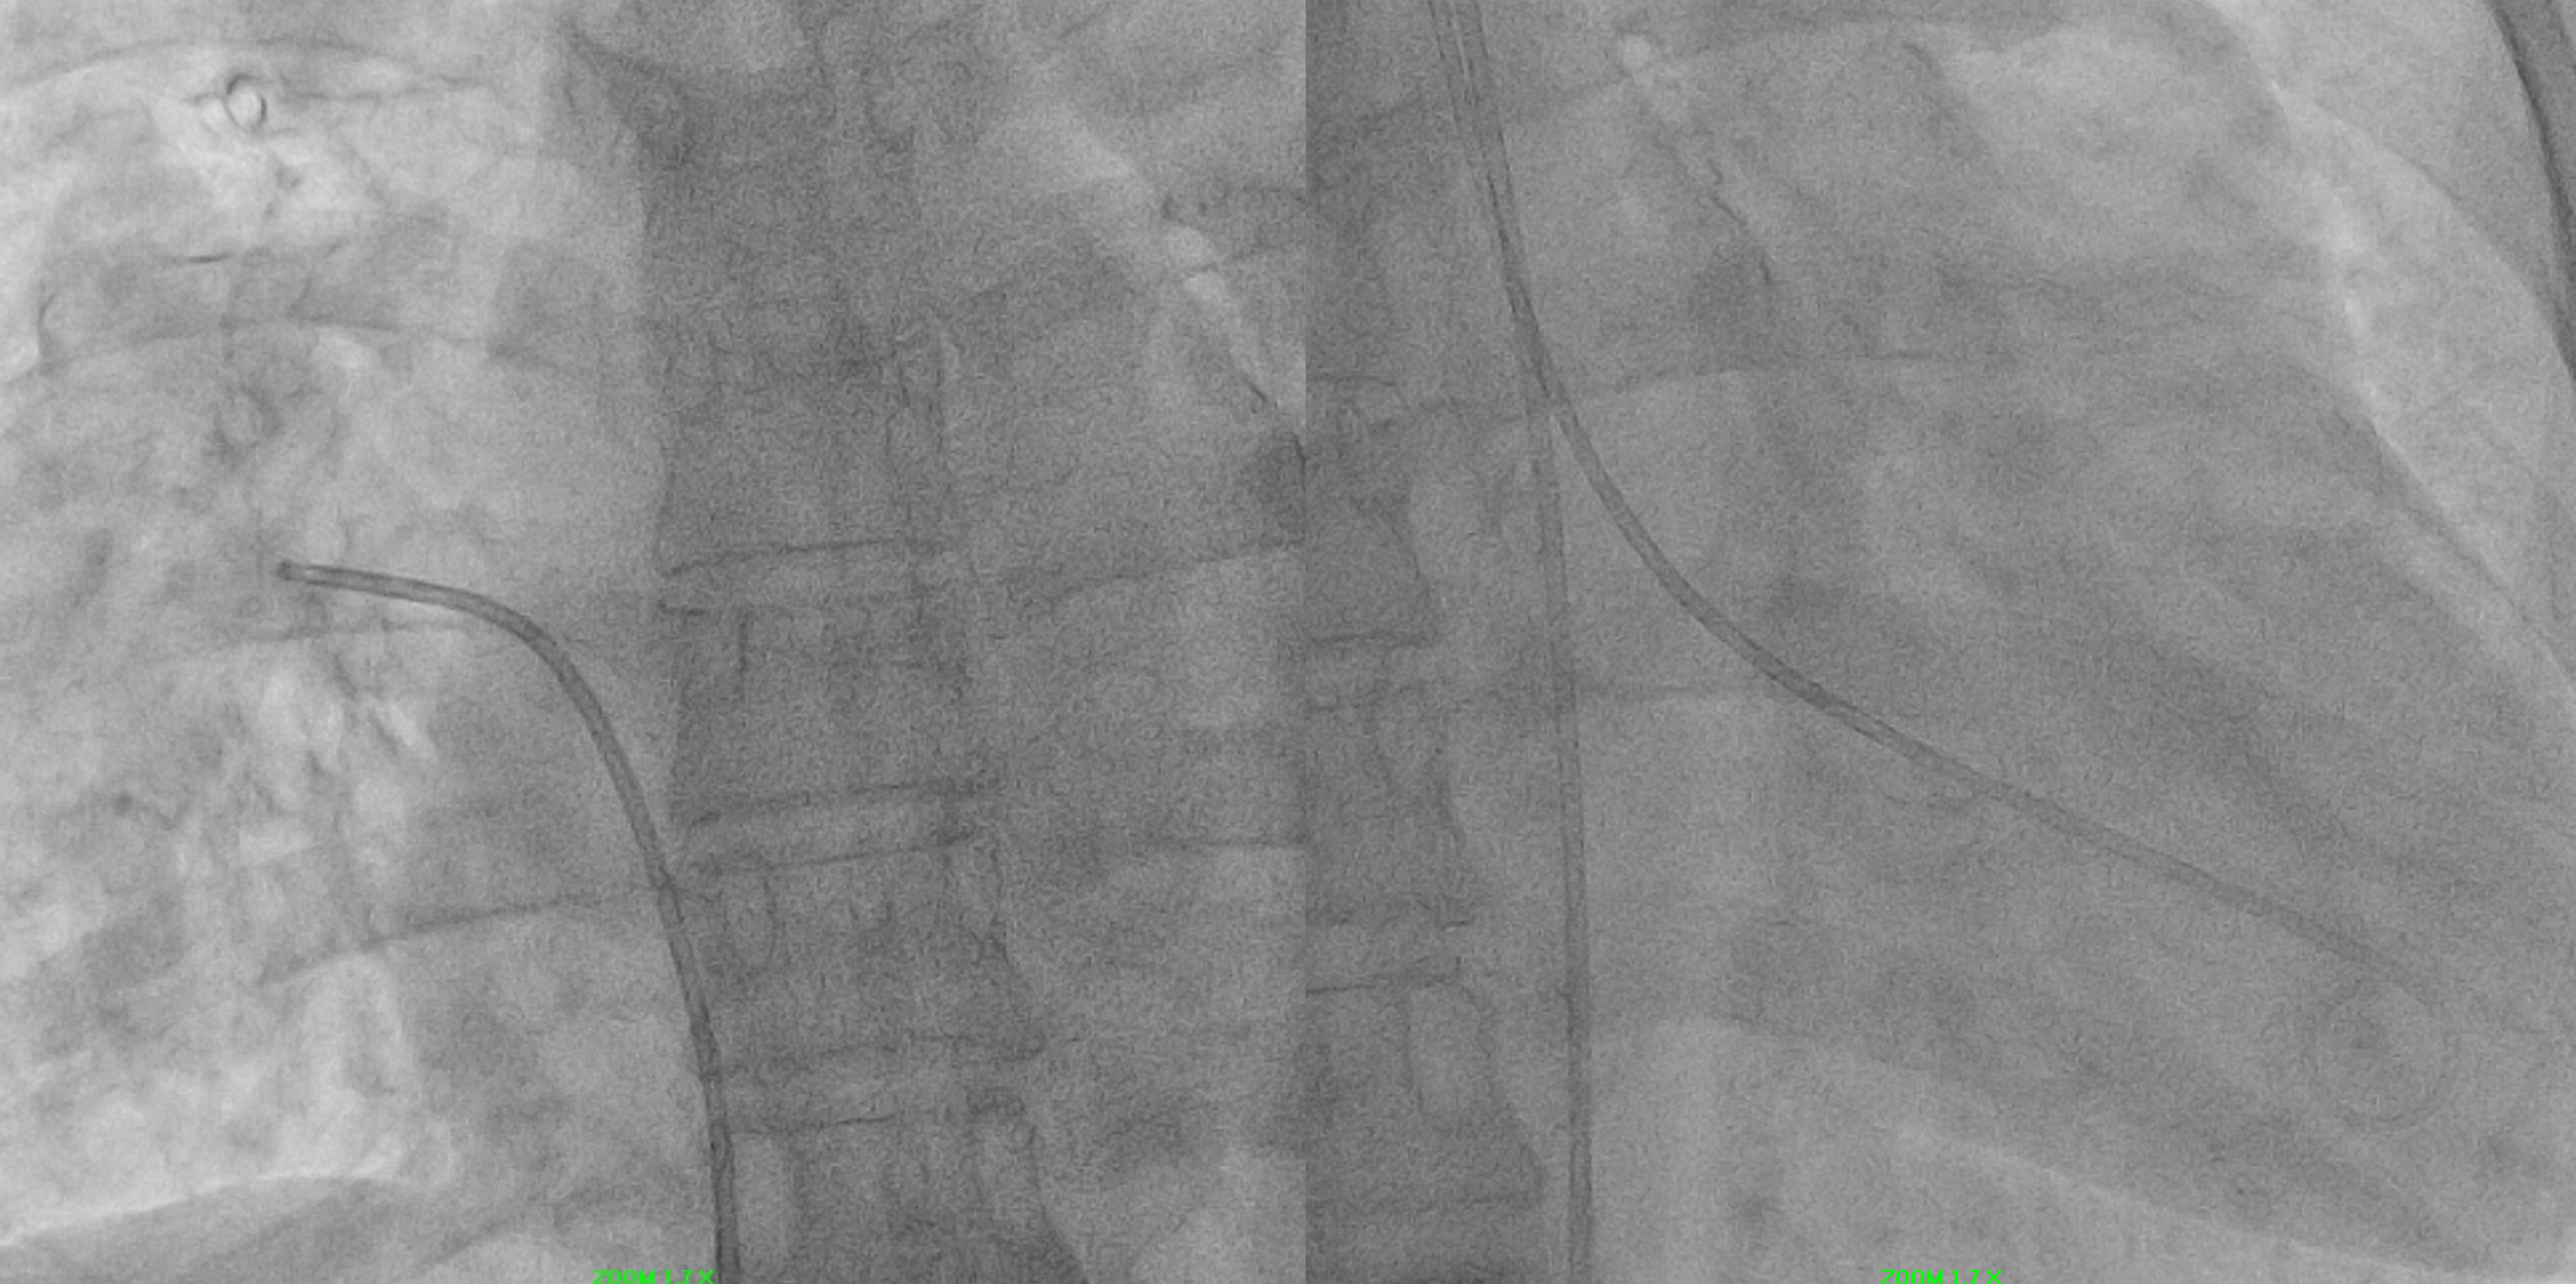

IVUS pullback performed:

Dynamic compression of LMCA externally (MLA reduction by 47.3%, from 12.8 to 6.74 mm2)Minimal intimal plaqueLAD, LCX, RCA was normal.

This case highlights our patient with longstanding secundum ASD and pulmonary arterial hypertension who developed dynamic left main coronary compression by a dilated pulmonary artery, confirmed on IVUS (MLA 12.8¡æ6.7 mm©÷, minimal plaque). Cardiac MRI showed Qp:Qs 1.86 and right-sided dilatation; right-heart catheterization revealed elevated but partially reversible PVR (4.9¡æ3.8 WU with iNO). A multidisciplinary, safety-first ¡°treat-and-reassess¡± strategy (targeted PAH therapy with planned fenestrated ASD closure if PVR improves) avoided premature high-risk interventions and provides a practical framework for similar complex ACHD patients.